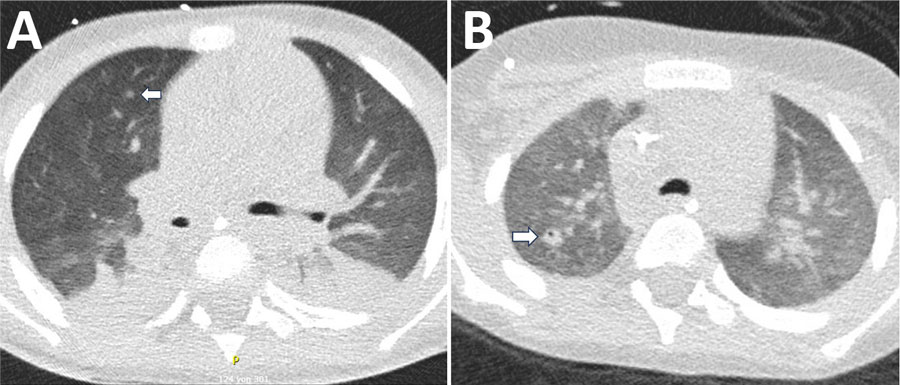

Figure 2. Chest computed tomography scan of a 4-year-old male patient with acute myeloid leukemia in study of Bjerkandera spp. pulmonary infection in immunocompromised hosts, Germany. The patient experienced fever unresponsive to antimicrobial treatment. A) Imaging revealed nodular infiltrates and surrounding ground-glass opacities in both lungs (arrow). Bjerkandera spp. was identified from tracheal aspiration. B) Follow-up computed tomography scan after 4 weeks demonstrated regressive nodular lesions and the formation of a cavity in the right upper lobe (arrow).